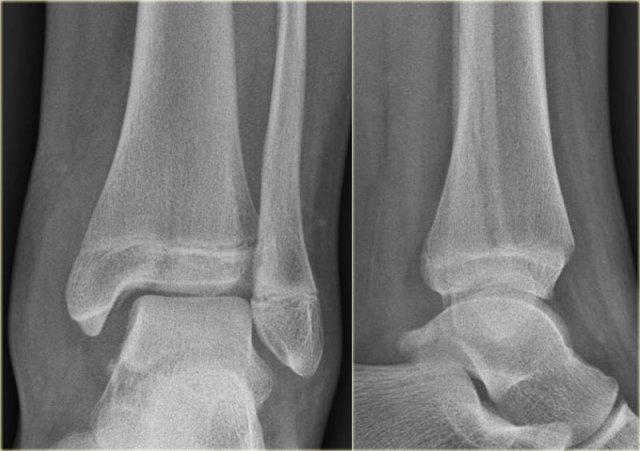

Đây là hình ảnh của một ca bệnh cực kỳ khó.

Bệnh nhân nữ bị bong gân cổ chân và đau cả hai bên trong và ngoài.

Bệnh nhân được bác sĩ đa khoa chuyển đến khoa Chẩn đoán Hình ảnh.

Kỹ thuật viên chụp các tư thế chuẩn gồm thẳng (AP), Mortise và nghiêng, sau đó trình bày cho bác sĩ X-quang, người đã khá băn khoăn khi đọc phim.

Hãy đọc hình ảnh trước, sau đó tiếp tục đọc phần giải thích.

Các dấu hiệu bao gồm:

-

Phù nề phần mềm cả hai bên trong và ngoài (mũi tên đỏ).

Đặc biệt, phù nề phía trong nên gợi ý khả năng chấn thương xoay ngoài – sấp (Weber C). - Đường thấu quang trên tư thế Mortise (mũi tên đen) và tư thế nghiêng. Dấu hiệu này nên gợi ý gãy tertius.

Bác sĩ X-quang quyết định chỉ định CT trước để xác định xem có thực sự có gãy tertius hay không.

Tiếp tục xem hình ảnh CT và bạn sẽ ngạc nhiên.